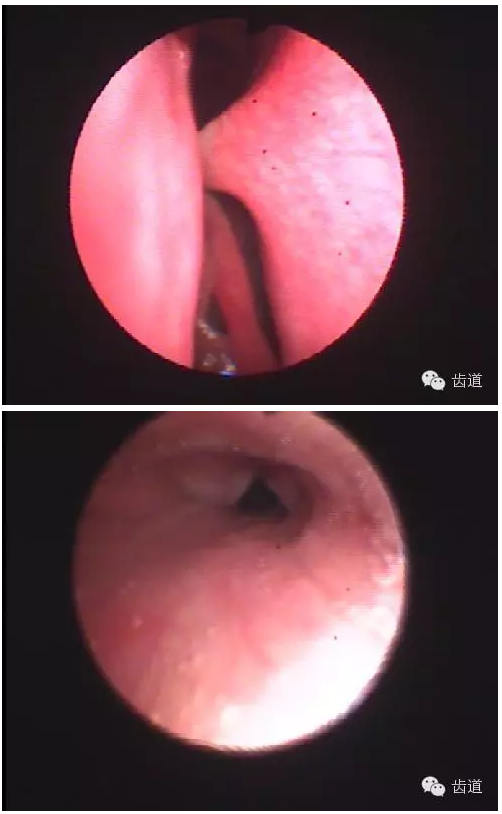

4.關(guān)節(jié)內(nèi)鏡檢查-直觀

可發(fā)現(xiàn)早期病變